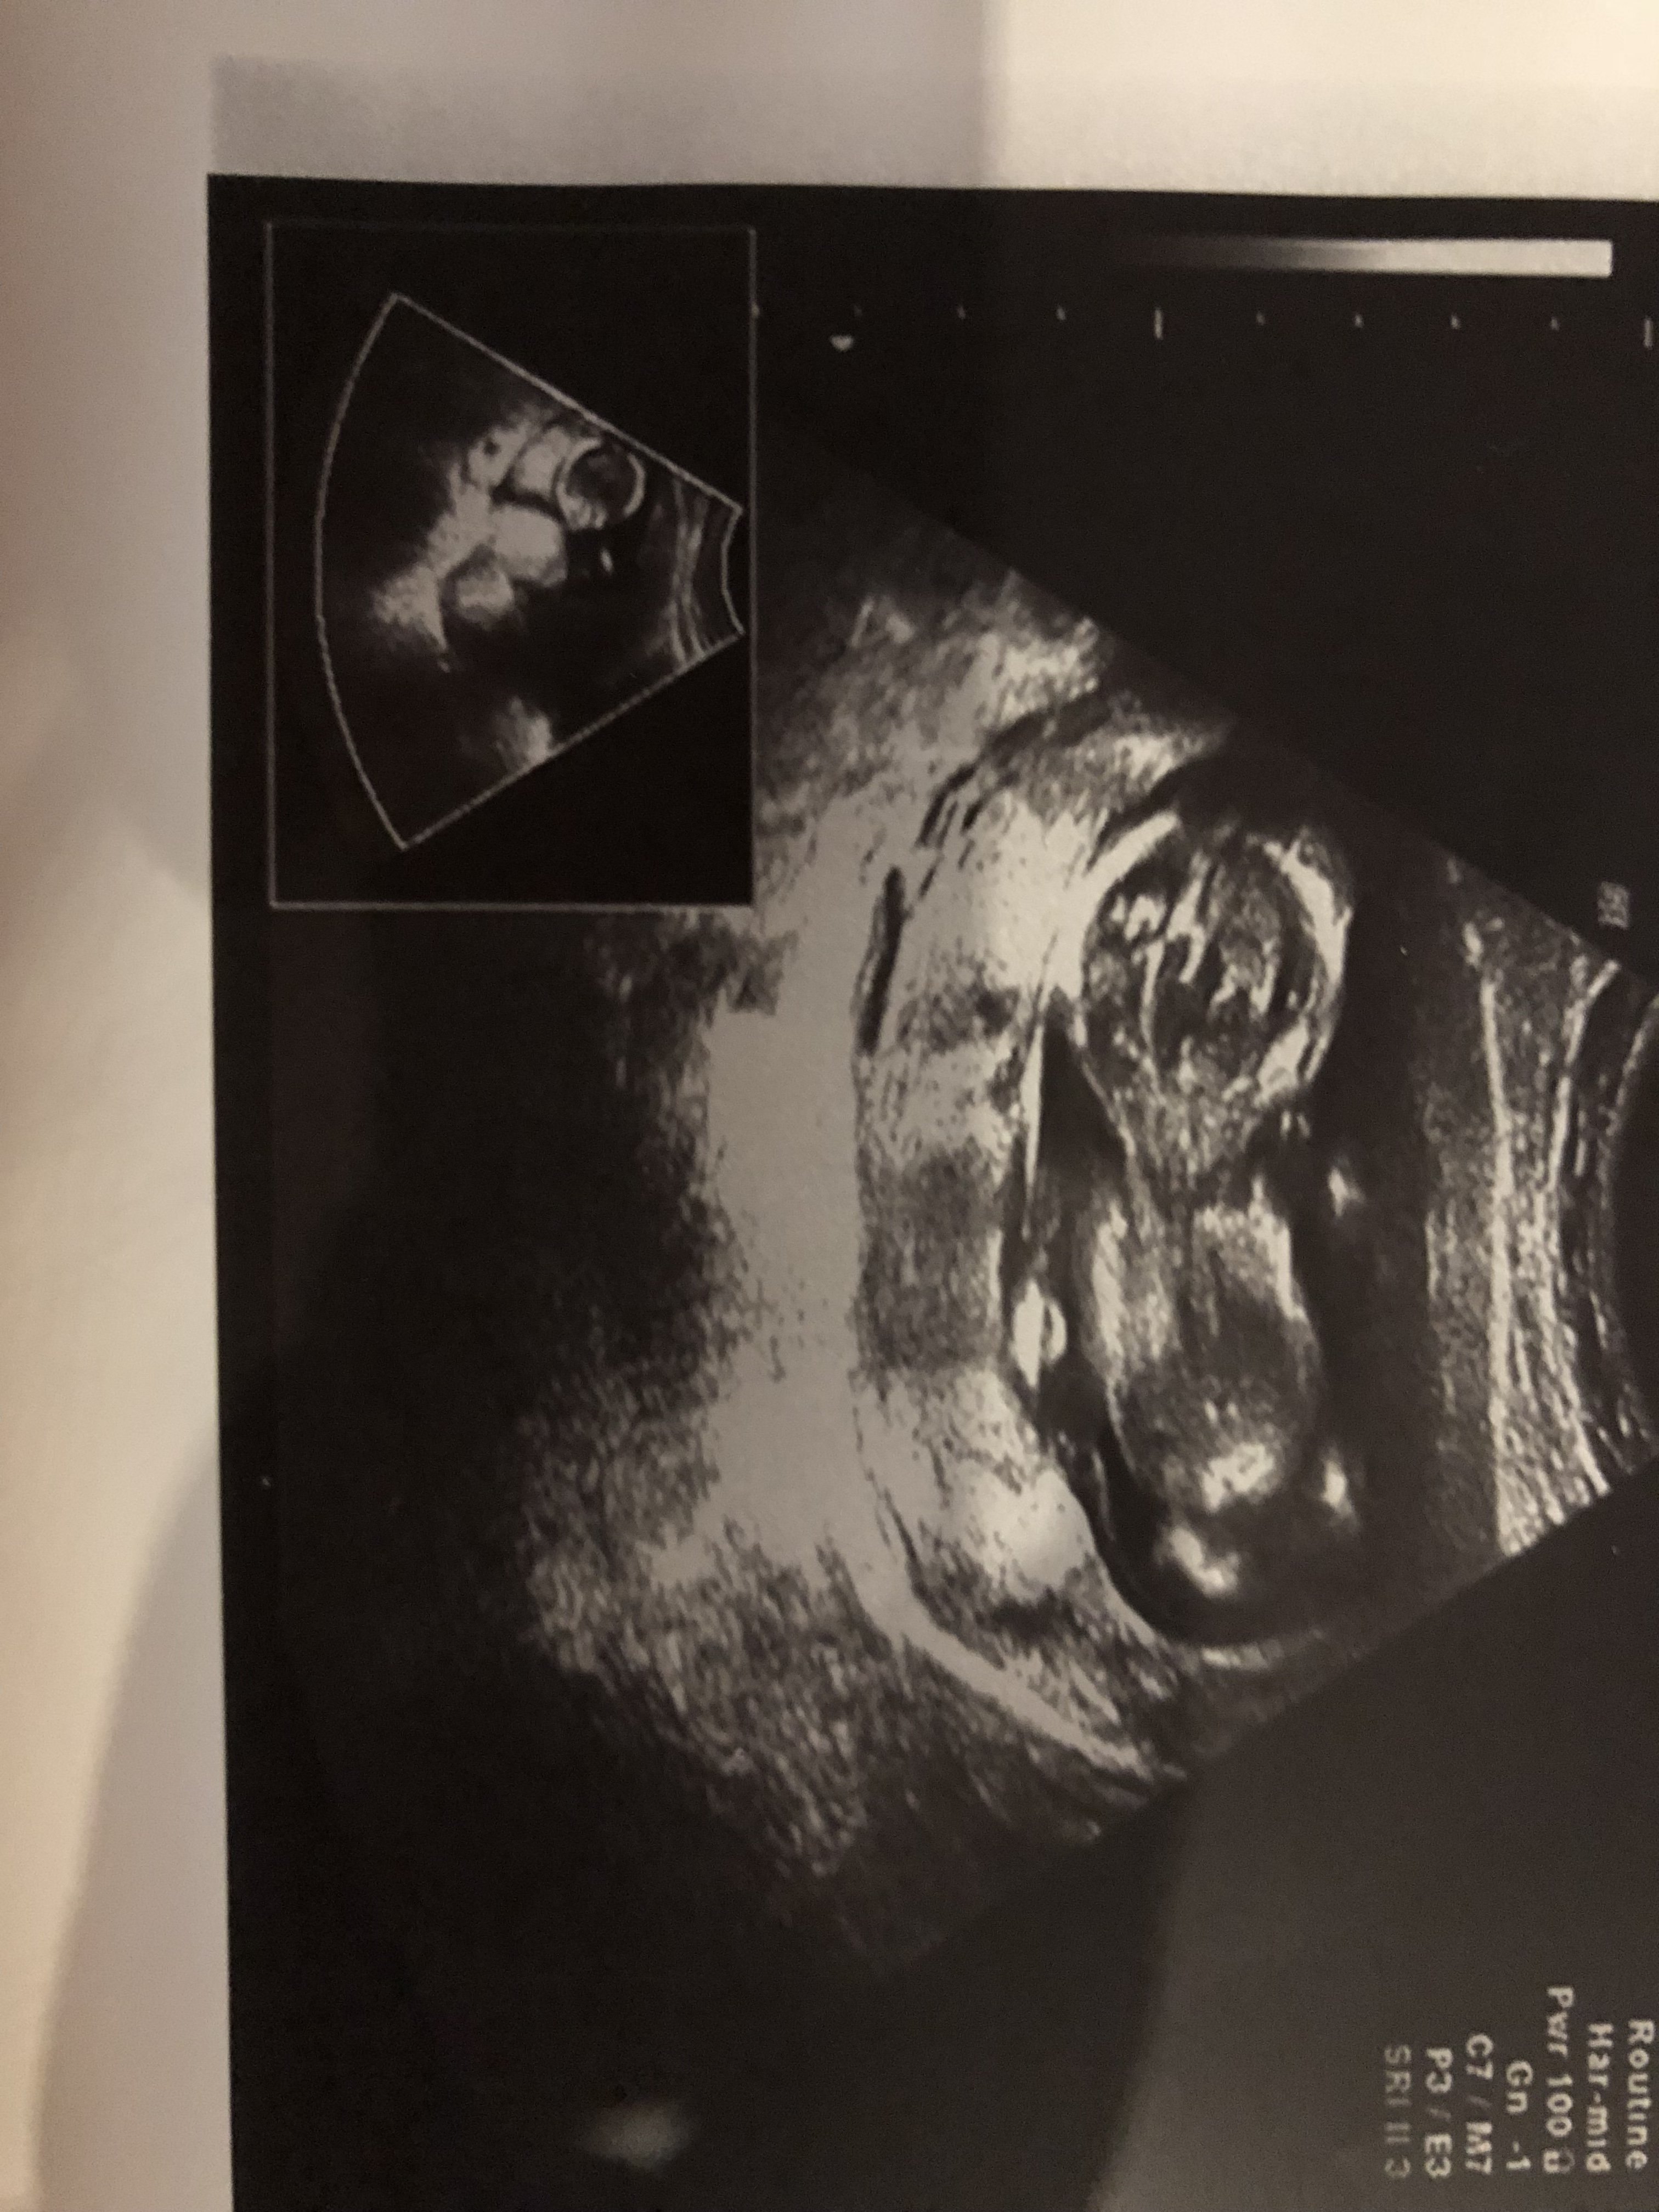

Witam w 19 tygodniu ciąży dowiedziałam się ze będę miała dziewczynkę w 20 tyg okazało się jednak , że to chłopak. Sama już nie wiem bo na jednym usg widać na pewno dziewuche a na drugim chłopca. Może to pempowina ?? Może ktoś mi pomoże rozwiązać ta zagadkę

Witam Was. Może po tych zdjęciach da się odczytać płeć dzidziusia? Dodam że jest to 12+4 tc na prenatalnych Pani dr nie była pewna zajrzała tylko między nóżki na wyrostek nie patrzyła.